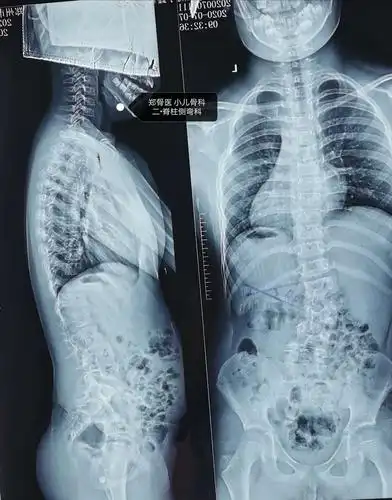

郑骨医,小儿骨科二脊柱侧弯科短阶段固定治疗脊柱侧弯一例

也叫作脊柱侧弯症,是一种常见的儿童骨科疾病,主要表现为脊柱弯曲畸形